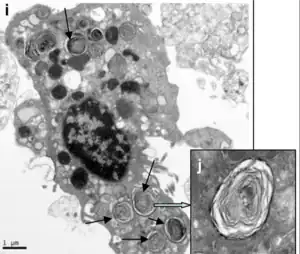

Se encuentran distribuidos en pequeños grupos entre los neumocitos tipo I. Tienen forma cúbica y poseen microvellosidades en su superficie libre apical. En su interior contienen una serie de vacuolas llamadas citosomas donde almacenan el surfactante pulmonar que secretan al alveolo mediante un proceso de exocitosis. El surfactante pulmonar se mezcla con agua reduciendo su tensión superficial y formando una fina capa que recubre toda la superficie alveolar.